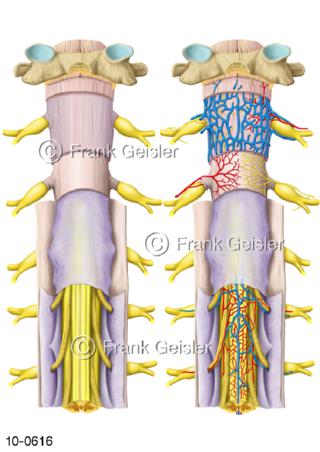

Bildergalerie Nervensystem

Bilder zum Nervensystem,dem Gehirn, Teil des zentralen Nervensystem, Zentralnervensystem ZNSmit Rückenmark, Abbildungen zum Nervengeflecht (Nervenplexus), die Verflechtungen von Nervenfasern, aus der Wirbelsäule hervortretende Nervenäst sowie Nervenzellen der Nerven